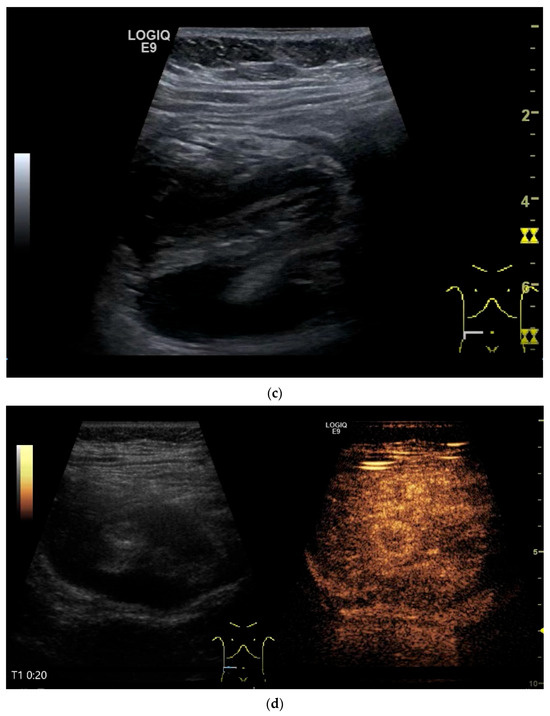

Figure 11.

GIST. A 30 mm large, very hypoechoic, almost anechoic round mass is visible in the left upper abdomen. This is located in the jejunum; the wall (W) and lumen (L) are visible (a). Macro vessels can be distinguished on Power Doppler, demonstrating that the lesion is solid and not cystic (b). On CEUS with 2.4 mL SonoVue (linear transducer 9 MHz), a small wheel-spoke-like vascular branching is visible at the margin (arrow) (c) with centrifugal enhancement (arrow) (d). Hyperenhancement is heterogeneous in the early arterial phase (e,f) and becomes homogeneous in the later course of the arterial phase (g). The extent of the heterogeneously enhanced tumor is marked with arrows (e). The intensity of the enhancement decreases during the first minute. The tumor is marked with arrows (h). Jejunal segment resection revealed the histology of an epithelioid GIST.